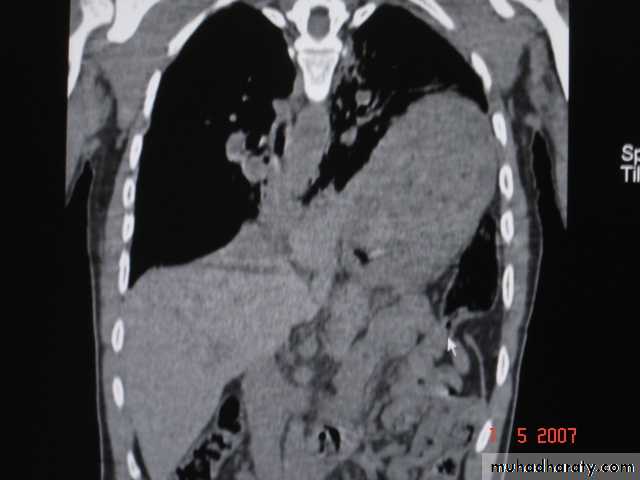

• Pulmonary Echinococcosis (Hydatid Cyst)

• Hydatid disease of the lung is caused by the small tape worm (Taenia Echinococcus ) or (Echinococcus Granulosis) .Hydatid cyst means cyst full of water .It has a life cycle between dogs & sheep .Parasites in the elementary tract of the dog shed ova that excreted in the dog faeces , contaminated the food of the sheep in which hydatid cyst will develops in the viscera . Including the lung .Infected sheep when slaughtered and its entrails are eaten by dogs , the life cycle is completed .When a human being hands or food become contaminated with canine fecal material containing ova which will be ingested .The parasitic larva burrow through the gastric mucosa and are carried to the liver in the portal venous circulation where most of them filtered out to form hydatid cyst of the liver , some escape the liver & lodge in the lung to form one or more hydatid cyst which grows slowly or rapidly over years .

• The cyst consists of a germinal layer & cyst fluid containing broad capsule & scoleses . A cellular white hyaline layers are laid down outside the cyst so that the cyst is enclosed by a laminated cyst membrane .As the cyst enlarged , it usually reaches the pleural surface . Compression of the lung tissues produces a thin fibrous layer of atelectatic lung tissue around the cyst (capsule , pericyst or adventia)

• Radiological Findings

• 1-Smooth homogenous opacity (Intact H.C).• 2-Partial rupture (per vesicular pneumocyst).

• 3-Complete rupture (Water –lilly sign) .

• 4-Formation of lung abscess(Air –fluid level) .

• 5-Completely coughed out cyst(empty cavity )

• 6-Rupture into the pleura (hydropneumothorax)